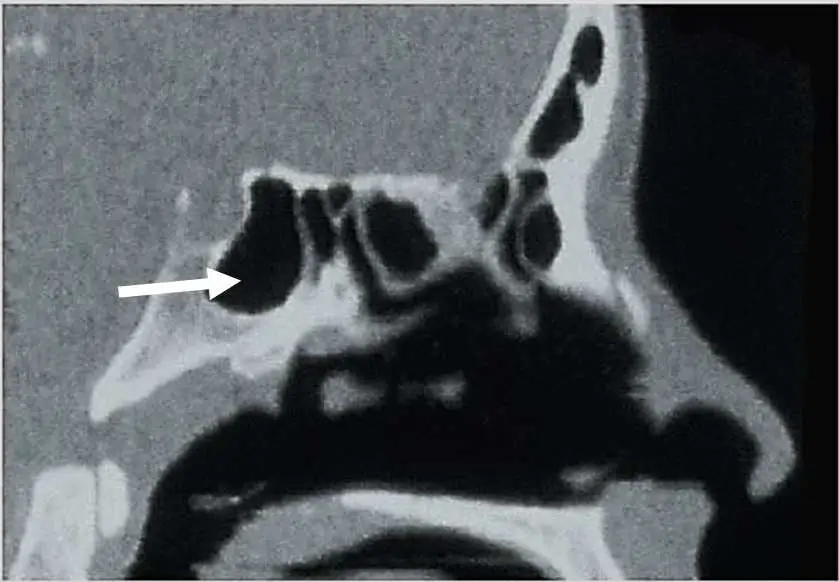

附圖 為一頭部 CT 矢狀切面圖,箭號所標示的構造為何?

本題附圖為頭部 CT 矢狀切面(sagittal view),影像為骨窗(bone window),顯示顱底中線區域的氣腔結構:

- 影像右側(前方)可見鼻腔輪廓及上方的額竇區域(影像右上角較小的氣腔)。

- 影像中央偏後方有一較大的不規則氣腔,呈現低密度(黑色),代表充氣的竇腔。

- 白色箭號指向該氣腔位於後鼻腔正後方、顱底中央深部的位置,緊鄰蝶鞍下方。此氣腔的位置特徵——位於鼻腔後方、蝶鞍正前下方、頭顱中央深部——完全符合 蝶竇(sphenoidal sinus) 的解剖位置。

- 上方可見蝶鞍的骨性輪廓(高密度骨性標記),蝶竇位於其下。

- 額竇(frontal sinus)位於影像前上方,位置較淺;篩竇(ethmoidal sinus)位於鼻腔上方兩側;上頜竇(maxillary sinus)位於上頜骨內側面,不位於矢狀中線深部。

箭號所指為 **蝶竇(sphenoidal sinus